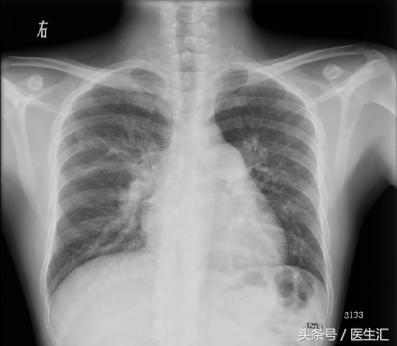

【胸片】